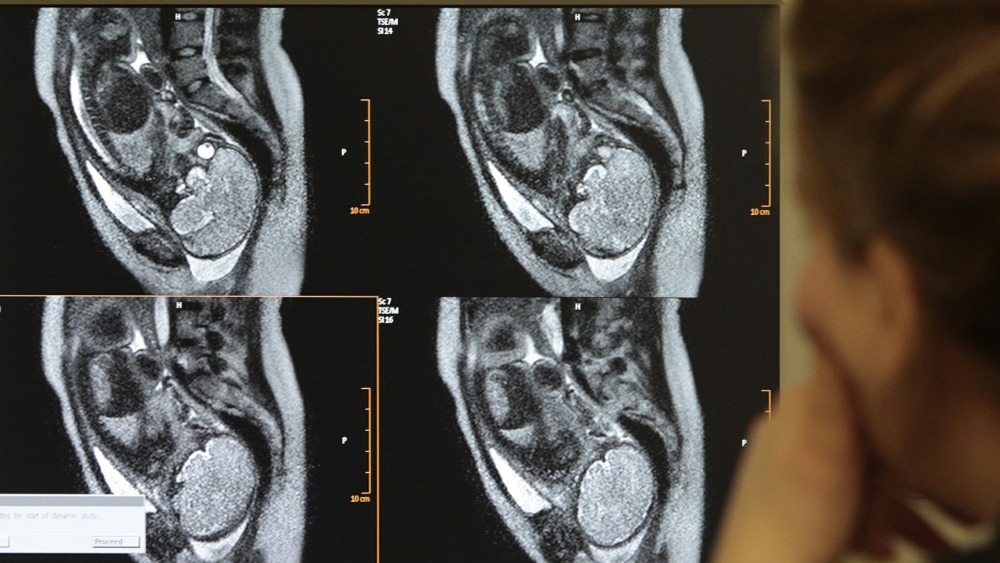

An MRI scan shows an unborn baby at 27 weeks. Baby mri scan video.

Up to 15 cash back An MRI scan shows an unborn baby at 29 weeks. Mri scan is done shortly after birth if any child suspected of having some kind of.